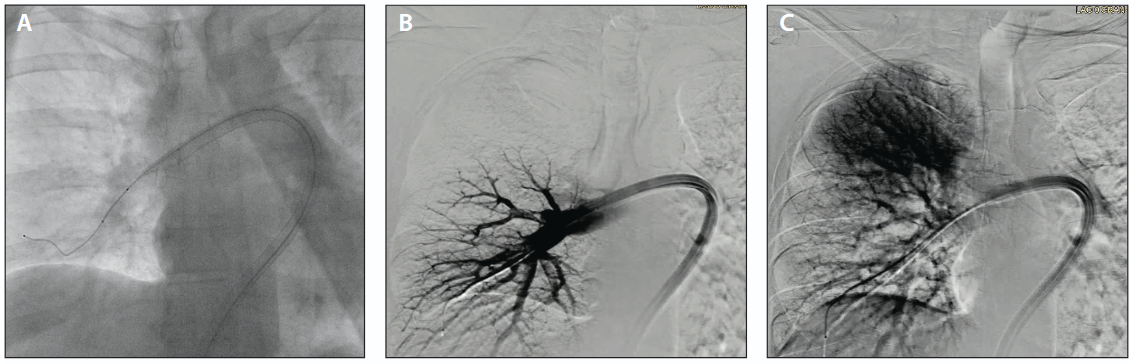

The AVENTUS Thrombectomy System was selected for thrombectomy of both the right and left pulmonary arteries. Starting with the right side, the catheter was introduced via the femoral vein and advanced over a Hi-Torque Supra Core (Abbott) guidewire using the system’s integrated 4-F guide catheter, allowing for efficient navigation through the dilated right ventricle to the right pulmonary artery (Figure 3). The integrated dilator tip and directional aspiration eliminated the need for any dilator or catheter exchange before the initial aspiration. Initial aspirations successfully removed the clot, and the catheter was advanced and rotated to target the truncus for additional aspirations, which removed most of the clot on the right side. Navigating to the left side was achieved by simply retracting the catheter and redirecting the integrated wire and guide catheter into the left pulmonary artery (Figure 4A). The catheter was then advanced into the left lower posterior lobe. Aspirations were performed to remove clot from the left side, and a final angiogram was taken (Figure 4B). After each aspiration, blood and clot collected in the aspiration syringe was transferred into the blood filtration chamber by simply depressing the syringe plunger. The one-way valve integrated into the syringe tip automatically diverts the flow into the blood filtration chamber for filtration and return to the patient. Immediate postprocedure improvements included a reduction in right atrial pressure from 20 to 15 mm Hg and a drop in pulmonary artery pressure from 60/24 to 30/20 mm Hg.

Figure 3. Intervention of the right pulmonary artery with AVENTUS system, with aspiration port pointing caudal (A). Selective angiogram of the right lower lobe showing resolution of large thrombotic burden (B) and perfusion or blush noted in the upper aspect of the right lung (C).